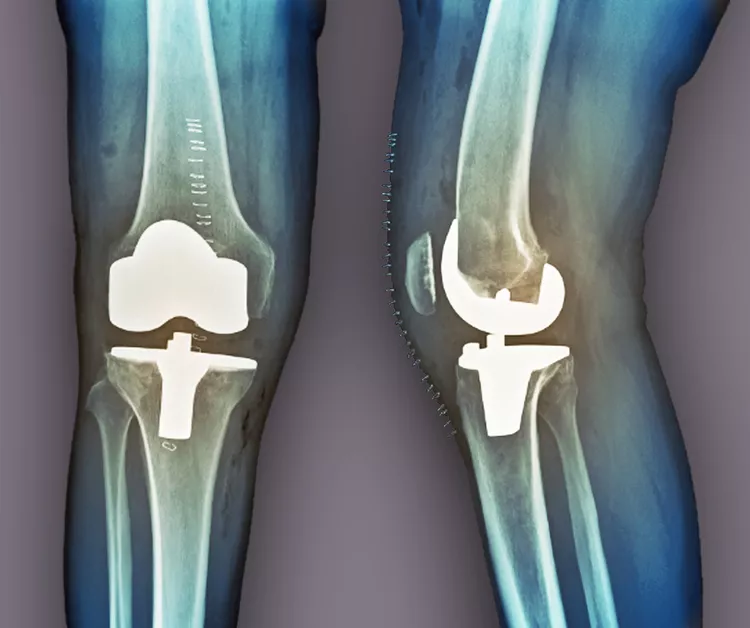

膝骨關節炎的后期治療

當其他療法失敗時,關節置換術是最后選擇。在這種手術中,醫生會切除膝蓋受損部位,并用金屬或塑料部件代替。如果這種方法不起作用,通過融合連接骨頭可能會緩解疼痛。缺點是,在這種手術后,其他關節最終會承受更大的壓力,以補償融合關節的運動損失。